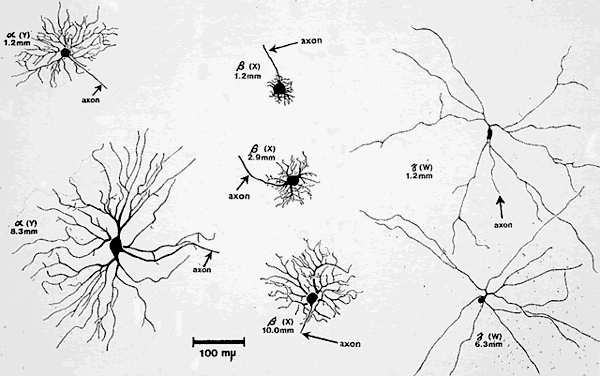

GANGLION CELL INPUT

Although it appears that the pupillary and visual systems share the same photoreceptor input (and presumably bipolar cell input), the role of ganglion cell input is far less clear. Over the years, many anatomic and physiologic studies have been carried out in an attempt to classify retinal ganglion cells based on the their cell body size, dendritic field, axonal diameter, and electrical firing properties. This information has been collected in a number of species, most notably the cat and monkey, and the projections of the cell axons to the lateral geniculate body and midbrain have been studied with the use of labeling techniques. Loewenfeld24 summarized the properties of the major classes of ganglion cells in the retina and their projections. Based on these studies, there appear to be three main types of ganglion cells that make up the retina in primates: the alpha, beta, and gamma cells. In the cat, these correspond to the Y, X, and W cells, respectively (Fig. 11).

Fig. 11. Size and shape of three chief types of retinal ganglion cells (cat), as described by Boycott and Wässle in 1974. All drawings are to the same scale, shown at the lower edge. The numbers given for each cell indicate its distance from the center of the central area of the retina. Alpha cells correspond to Y or “brisk-transient” cells (left), beta cells to X or “brisk-sustained” (middle), and gamma cells to W or “sluggish” cells of other terminologies (right). Note that the dendritic trees of the alpha and beta cells increase in size with eccentricity, but those of the gamma cells do not. The dendritic configurations differ markedly among the three groups of cells and are much smaller in beta cells than in alpha and gamma cells. (Boycott BB, Wässle H: The morphological types of ganglion cells of the domestic cat's retina. J Physiol 240:397, 1974)